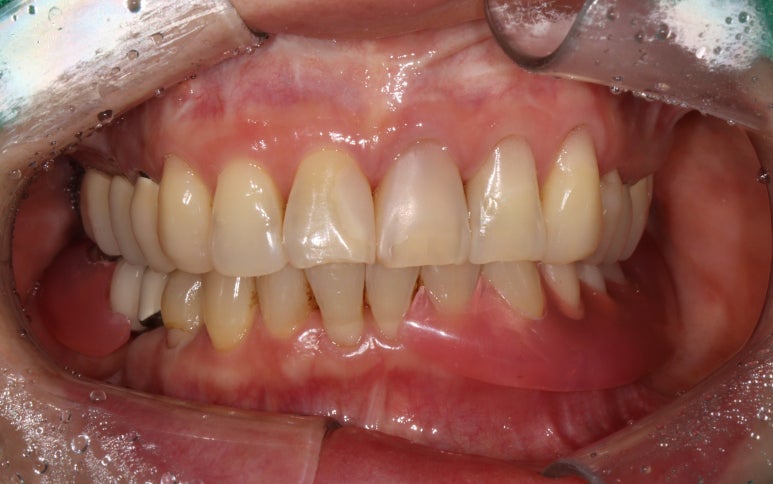

왼쪽 아래 어금니의 임플란트 보철물을 모두 만들고 나서의 임상 사진입니다.

자세히 보시면, 맨 뒤 어금니의 바깥쪽으로 단단하게 보이는 부착치은 (각화치은)이 잘 생착되어 있는 것을 보실 수 있어요!!

편하게 양치질을 하게 해주고, 임플란트 주변에 음식물이 끼는 것을 최대한으로 막아준답니다.

그래서 임플란트 주위염의 발생 가능성을 현저히 낮추고, 결과적으로 어금니 임플란트를 오래 쓸 수 있게 해주죠.

자연치 저작기능의 30%도 가져갈 수 없는 한쪽 틀니에서,

임플란트로 교체하시면서 씹어먹는 기능에 대해 큰 만족도를 표하셔서 너무 기뻤습니다.